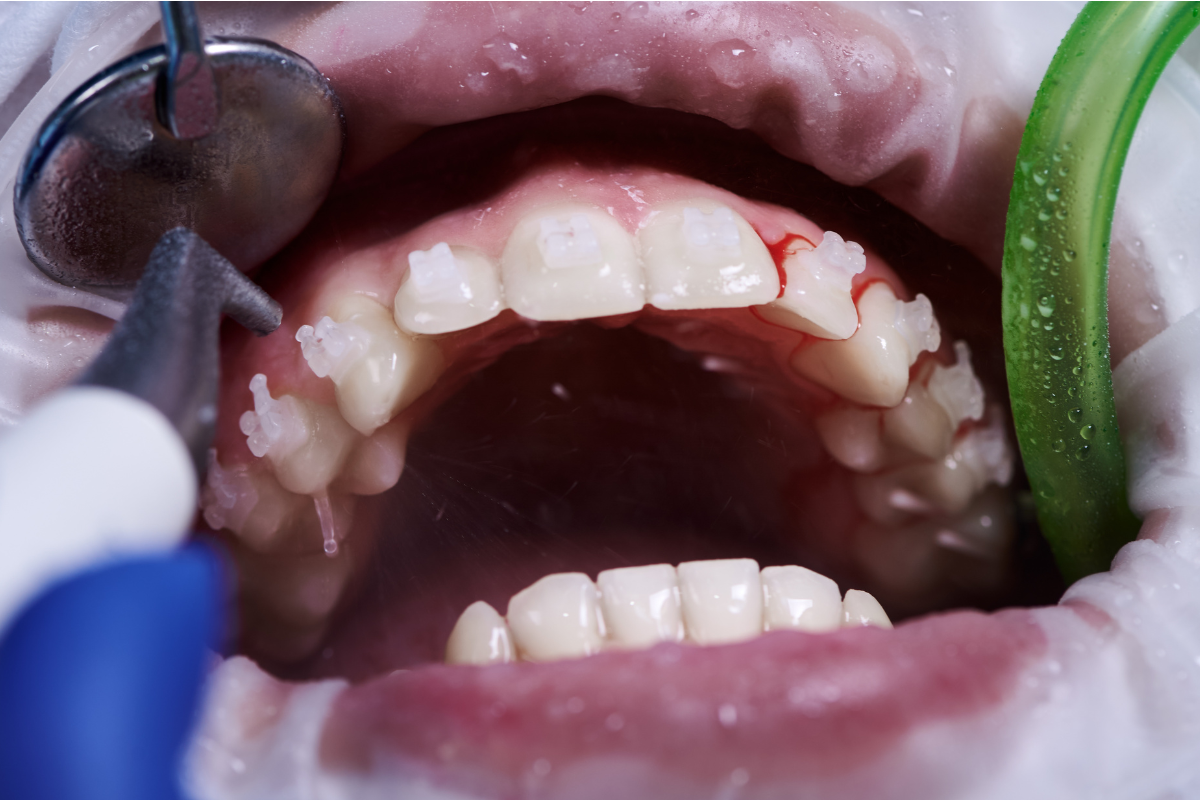

Plaque is a sticky film of bacteria that forms on your teeth after eating and drinking. If you don’t remove plaque with daily brushing and flossing, it hardens into tartar, which can only be cleaned by a professional. Tartar buildup irritates the gums, causing them to swell, bleed, and pull away from the teeth. This is the earliest stage of gum disease, known as gingivitis. Without professional care from a dentist in Rancho Santa Margarita, gingivitis can progress to periodontitis, a more advanced stage that damages the bone and connective tissues supporting your teeth.

- Bleeding during brushing or flossing